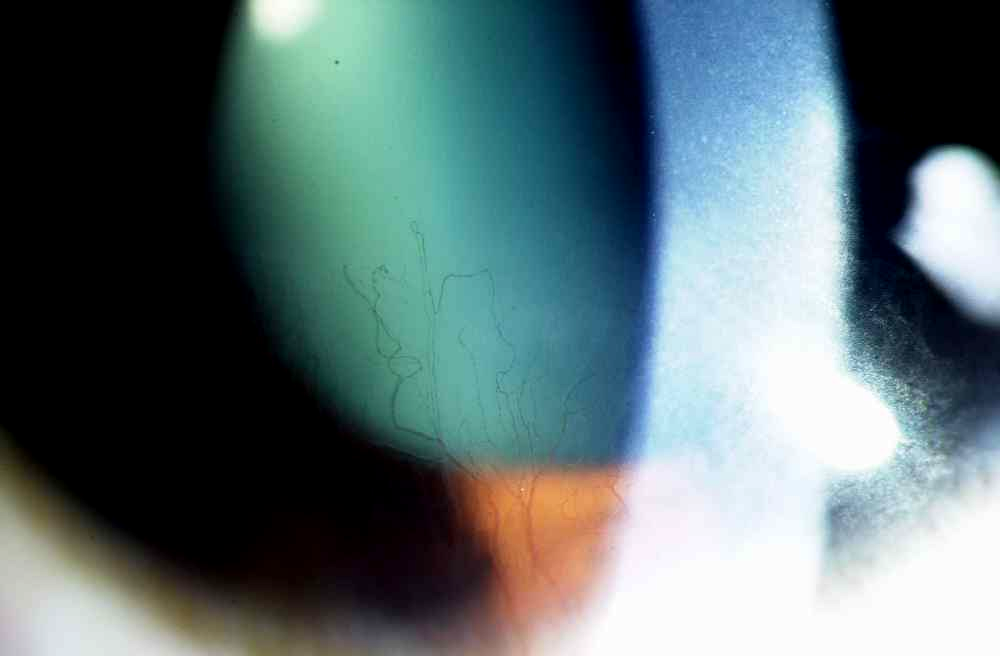

3、间接照明法

间接照明法是将光线照射在组织的一部分上,而观察其邻近的同一组织的另一部分。

如通过晶状体间接照明观察后发性白内障、通过角膜间接照明观察角膜新生血管。

间接照明法使后发障和角膜新生血管清晰可见